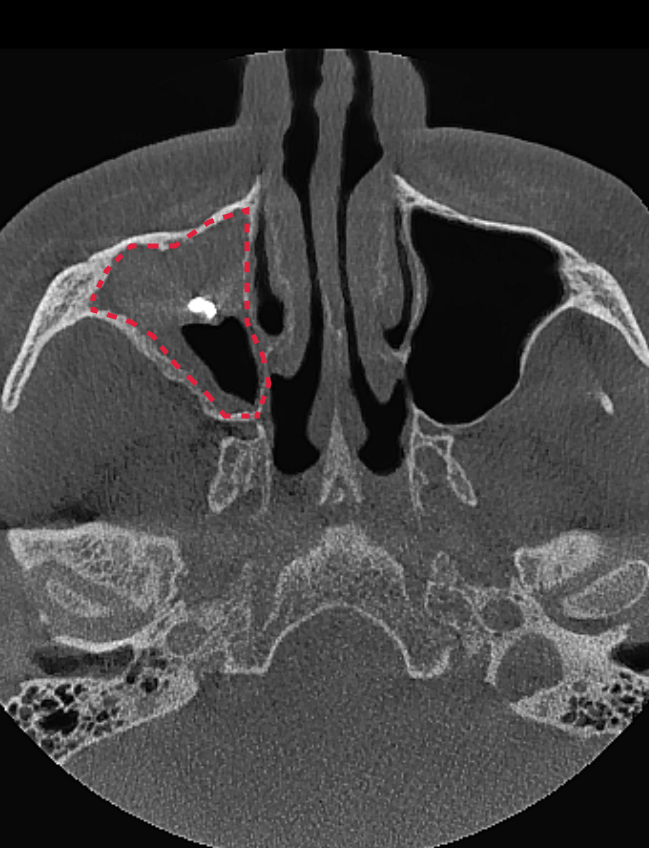

Подготовка к синус-лифтингу. Компьютерная томография до ЛОР-лечения. На снимке видим инородное тело и грибковую ткань в пазухе. Синус-лифтинг проводить нельзя.